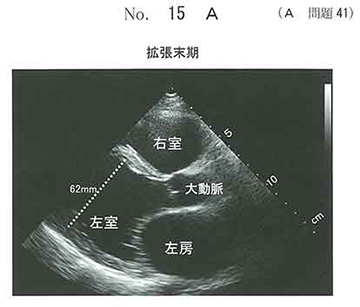

急性左心不全を伴うDCM。